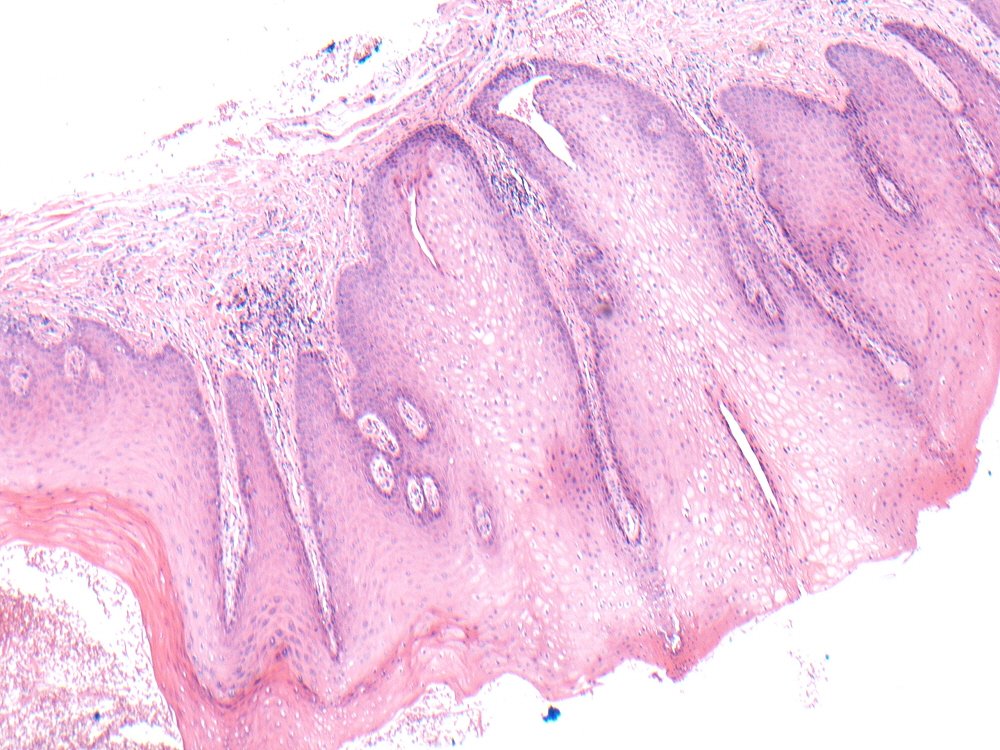

Smokers Palate Histology

Smokers Palate Histology What Is Smokers Palate nicotine stomatitis, also often called smoker's palate, is a reaction seen on the roof of the mouth caused by extreme. smoker's palate is a type of lesion that occurs on the mucosa of the hard and soft palate almost exclusively in. nicotinic stomatitis (smoker's palate), a lesion of the palatal mucosa, has been described in the literature. What Is Smokers Palate.

Smokers Palate Histology What Is Smokers Palate smoker's palate is a type of lesion that occurs on the mucosa of the hard and soft palate almost exclusively in smokers. nicotine stomatitis, also often called smoker's palate, is a reaction seen on the roof of the mouth caused by extreme. nicotinic stomatitis (smoker's palate), a lesion of the palatal mucosa, has been described in the. What Is Smokers Palate.

Smokers Palate Histology What Is Smokers Palate nicotinic stomatitis (smoker's palate), a lesion of the palatal mucosa, has been described in the literature since 1926. nicotine stomatitis, also often called smoker's palate, is a reaction seen on the roof of the mouth caused by extreme. smoker's palate is a type of lesion that occurs on the mucosa of the hard and soft palate almost. What Is Smokers Palate.

Smokers Palate Histology What Is Smokers Palate smoker's palate is a type of lesion that occurs on the mucosa of the hard and soft palate almost exclusively in. stomatitis nicotina is a diffuse white patch on the hard palate, usually caused by tobacco smoking, usually pipe or cigar. nicotine stomatitis, also often called smoker's palate, is a reaction seen on the roof of the. What Is Smokers Palate.

Smokers Palate Histology What Is Smokers Palate smoker's palate is a type of lesion that occurs on the mucosa of the hard and soft palate almost exclusively in. smoker's palate is a type of lesion that occurs on the mucosa of the hard and soft palate almost exclusively in. nicotine stomatitis, also often called smoker's palate, is a reaction seen on the roof of. What Is Smokers Palate.

Smokers Palate Histology What Is Smokers Palate smoker's palate is a type of lesion that occurs on the mucosa of the hard and soft palate almost exclusively in. nicotinic stomatitis (smoker's palate), a lesion of the palatal mucosa, has been described in the literature since. nicotine stomatitis, also often called smoker's palate, is a reaction seen on the roof of the mouth caused by. What Is Smokers Palate.

Smokers Palate Histology What Is Smokers Palate stomatitis nicotina is a diffuse white patch on the hard palate, usually caused by tobacco smoking, usually pipe or cigar. smoker's palate is a type of lesion that occurs on the mucosa of the hard and soft palate almost exclusively in smokers. smoker's palate is a type of lesion that occurs on the mucosa of the hard. What Is Smokers Palate.

Smokers Palate Histology What Is Smokers Palate stomatitis nicotina is a diffuse white patch on the hard palate, usually caused by tobacco smoking, usually pipe or cigar. nicotine stomatitis, also often called smoker's palate, is a reaction seen on the roof of the mouth caused by extreme. nicotinic stomatitis (smoker's palate), a lesion of the palatal mucosa, has been described in the literature since. What Is Smokers Palate.

Smokers Palate Histology What Is Smokers Palate smoker's palate is a type of lesion that occurs on the mucosa of the hard and soft palate almost exclusively in smokers. smoker's palate is a type of lesion that occurs on the mucosa of the hard and soft palate almost exclusively in. nicotine stomatitis, also often called smoker's palate, is a reaction seen on the roof. What Is Smokers Palate.

Smokers Palate Histology What Is Smokers Palate nicotine stomatitis, also often called smoker's palate, is a reaction seen on the roof of the mouth caused by extreme. stomatitis nicotina is a diffuse white patch on the hard palate, usually caused by tobacco smoking, usually pipe or cigar. nicotinic stomatitis (smoker's palate), a lesion of the palatal mucosa, has been described in the literature since. What Is Smokers Palate.